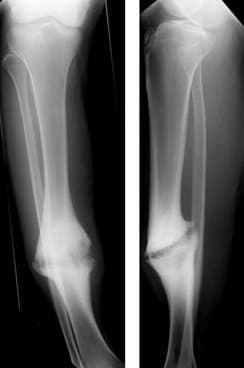

Nonunion is permanent failure of healing following a broken bone unless intervention (such as surgery) is performed. A fracture with nonunion generally forms a structural resemblance to a fibrous joint, and is therefore often called a "false joint" or pseudoarthrosis (from Greek pseudo-, meaning false, and arthrosis, meaning joint). The diagnosis is generally made when there is no healing between two sets of medical imaging, such as X-ray or CT scan. This is generally after 6–8 months. Nonunion is a serious complication of a fracture and may occur when the fracture moves too much, has a poor blood supply or gets infected. Patients who smoke have a higher incidence of nonunion. The normal process of bone healing is interrupted or stalled. Since the process of bone healing is quite variable, a nonunion may go on to heal without intervention in very few cases. In general, if a nonunion is still evident at 6 months post-injury it will remain unhealed without specific treatment, usually orthopedic surgery. A non-union which does go on to heal is called a delayed union. A history of a broken bone is usually apparent. The patient complains of persistent pain at the fracture site and may also notice abnormal movement or clicking at the level of the fracture. An x-ray plate of the fractured bone shows a persistent radiolucent line at the fracture. Callus formation may be evident but callus does not bridge across the fracture. If there is doubt about the interpretation of the x-ray, stress x-rays, tomograms or CT scan may be used for confirmation. The reasons for non-union are avascular necrosis (the blood supply was interrupted by the fracture) the two ends are not apposed (that is, they are not next to each other) infection (particularly osteomyelitis) the fracture is not fixed (that is, the two ends are still mobile) soft-tissue imposition (there is muscle or ligament covering the broken ends and preventing them from touching each other) Related to the person: Age: Common in old age Nutritional status : poor Habits : Nicotine and alcohol consumption Metabolic disturbance : Hyperparathyroidism Can be found in those with NF1 Genetic predisposition Causes related to fracture: Related to the fracture site Soft tissue interposition Bone loss at the fracture Infection Loss of blood supply Damage of surrounding muscles Related to treatment Inadequate reduction Insufficient immobilization Improperly applied fixation devices.